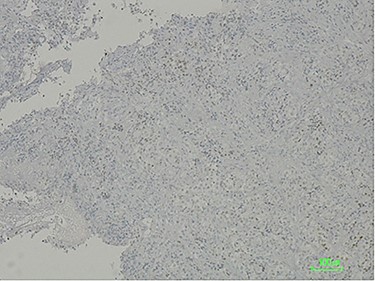

The histologic examination revealed a poorly differentiated adenocarcinoma, with a negative CDX2 and positive PAX8 immunostaining, hence compatible with a secondary lesion of endometrial origin (Figs 3 and 4).

Immunostaining positive for PAX8 suggesting a tumour of gynaecologic origin based on the patient’s past medical history.

CDX2 negative immunostaining excluding carcinoma of intestinal origin such as primary duodenal neoplastic lesion.

To this day, despite direct invasion being quite common, there have been very few reports of duodenal metastasis of malignancies originated in distant organs. Lung, renal, melanoma and colorectal cancer have sporadic reports of duodenal involvement [8, 9]. When identified on endoscopy, they frequently present as ulcerated lesions that can cause GI bleeding or gastric outlet obstruction. This finding is consistent with the endoscopy’s macroscopic description of the duodenal lesion and our patient’s clinical presentation. Immunohistochemistry provided the diagnosis after confirming its non-lower GI tract origin and gynaecologic related epithelial structure (positive for cytokeratin 7, negative CDX2 and positive PAX8 immunostaining) [3, 10].